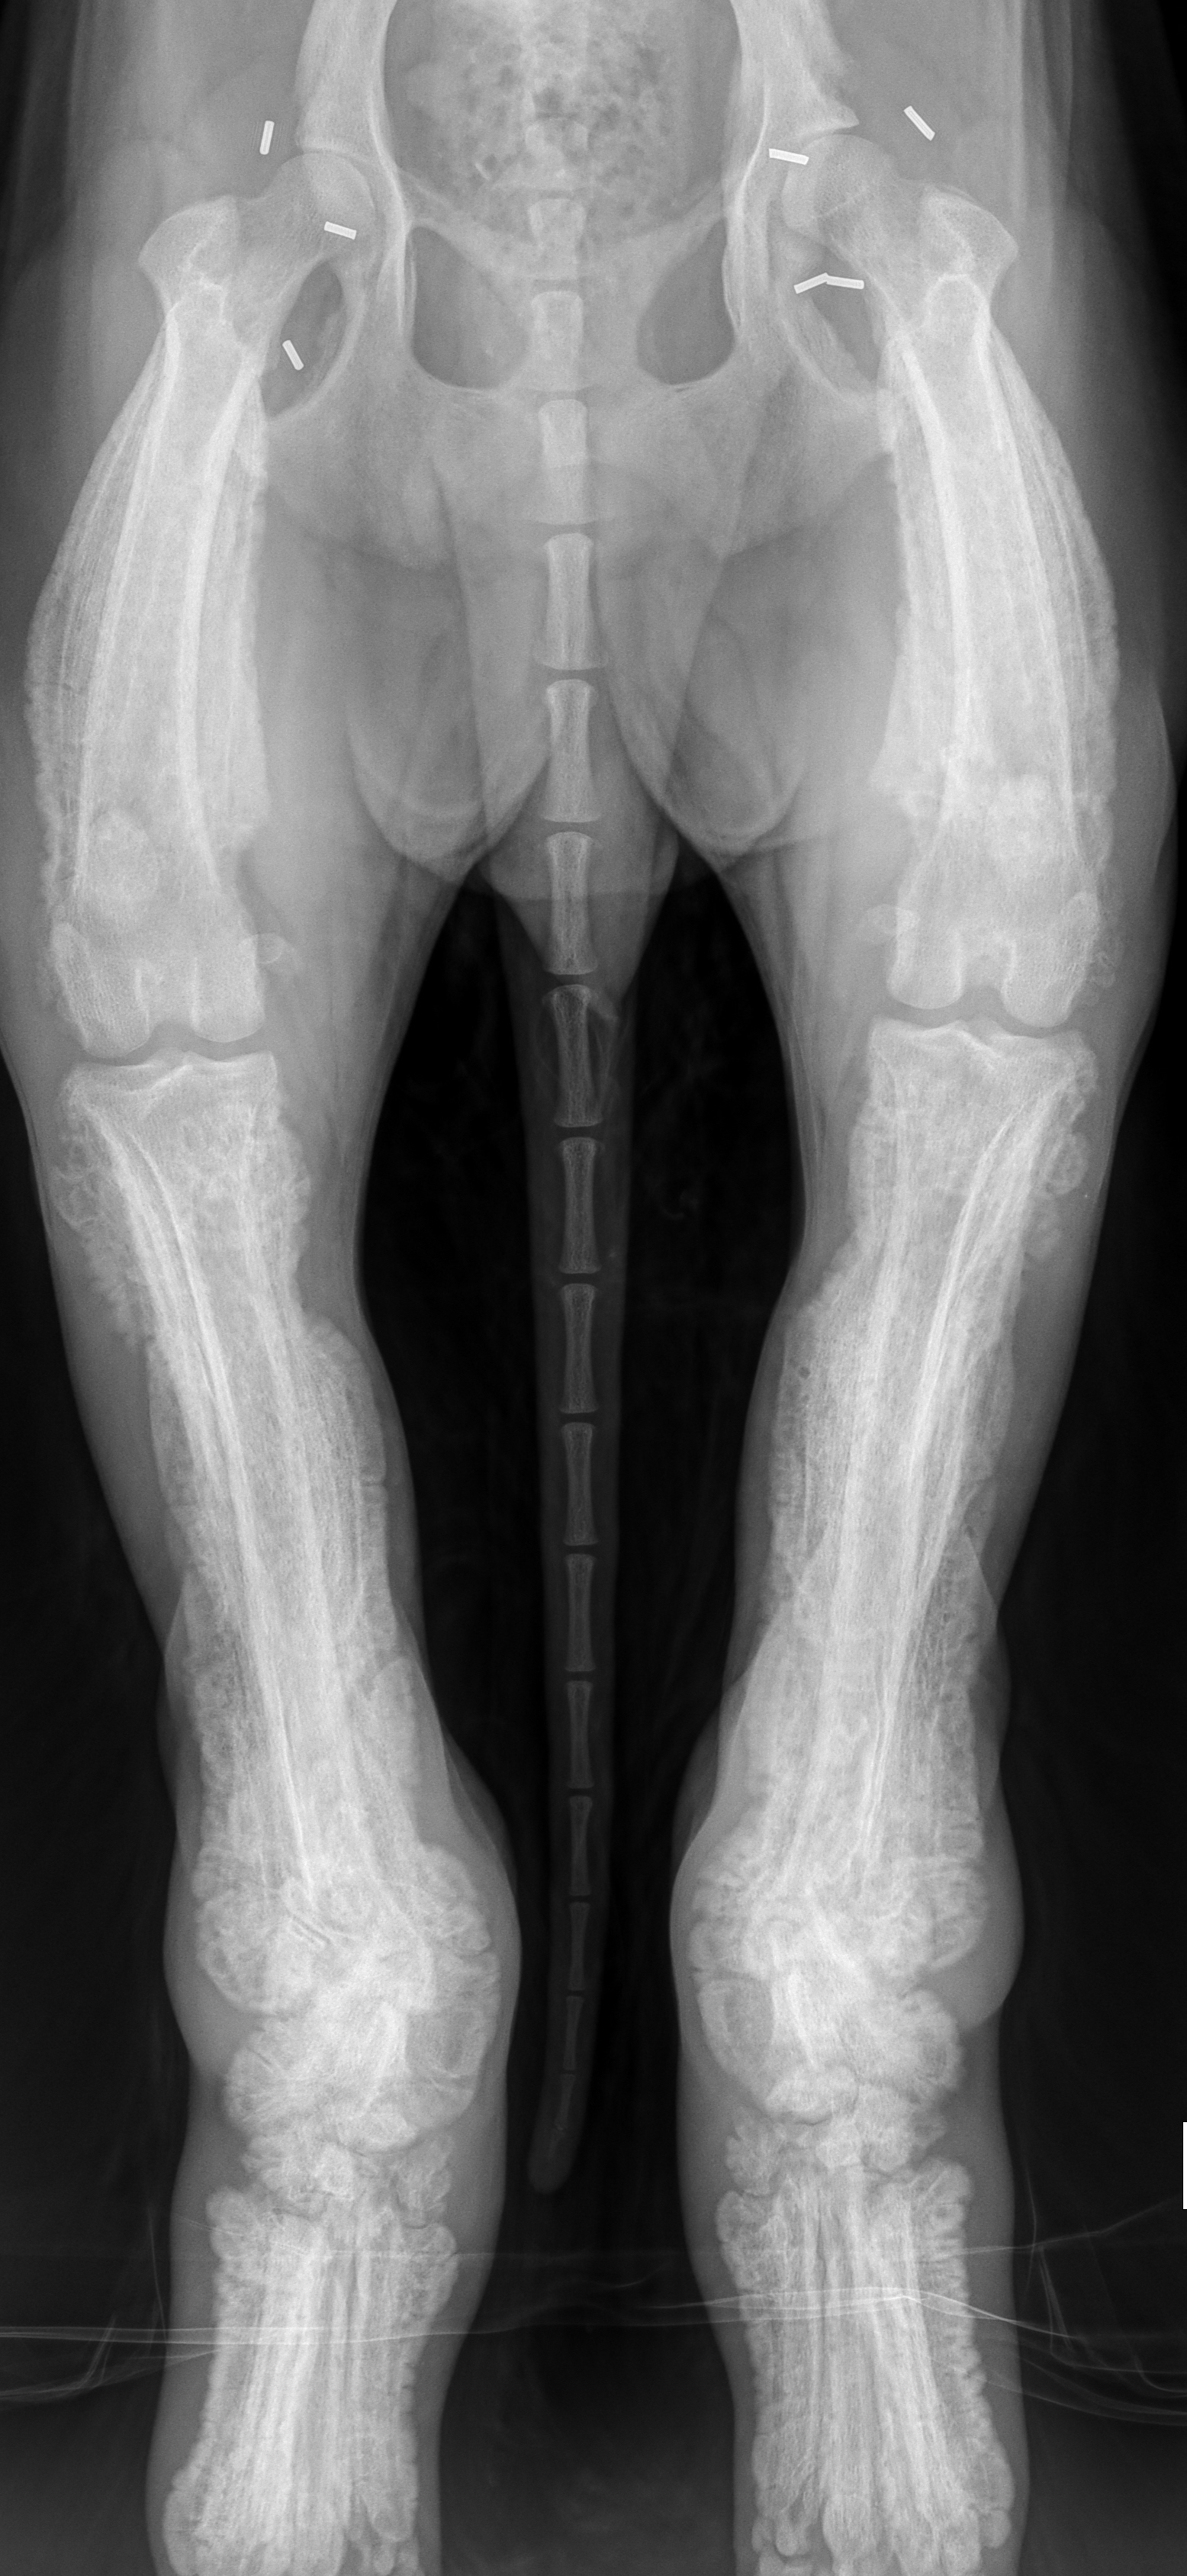

Bilateral symmetrische hochgradig spikula- bis palisadenähnliche periostale Reaktionen an den langen Röhrenknochen.